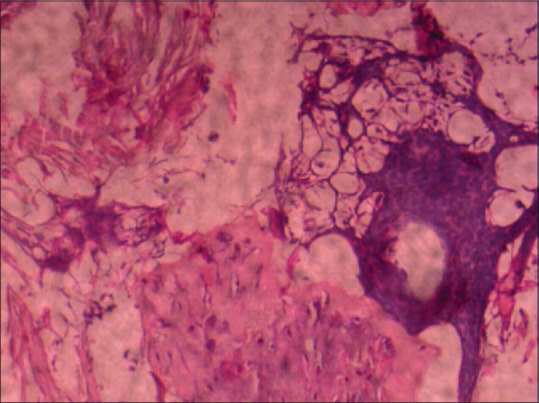

Osseous metaplasia (OM) of the cervix without involvement of the uterus is an extremely rare entity. Only few cases had been reported in the literature. We reported a rare case of OM of the cervix clinically mimicking cervical cancer. A 52-year-old female presented with chief complaints of leukorrhea and an unusual sensation of mass in the vagina. On clinical examination, the uterus, adnexa, pouch of Douglas, vulva, and perineum-all were normal except the cervix which was hypertrophied with surface irregularities. Histopathological examination of the cervix showed OM of the cervix. Since this is a benign entity, proper diagnosis is essential to avoid misdiagnosis of malignant tumors, especially malignant mesenchymal tumors.

Abstract Image